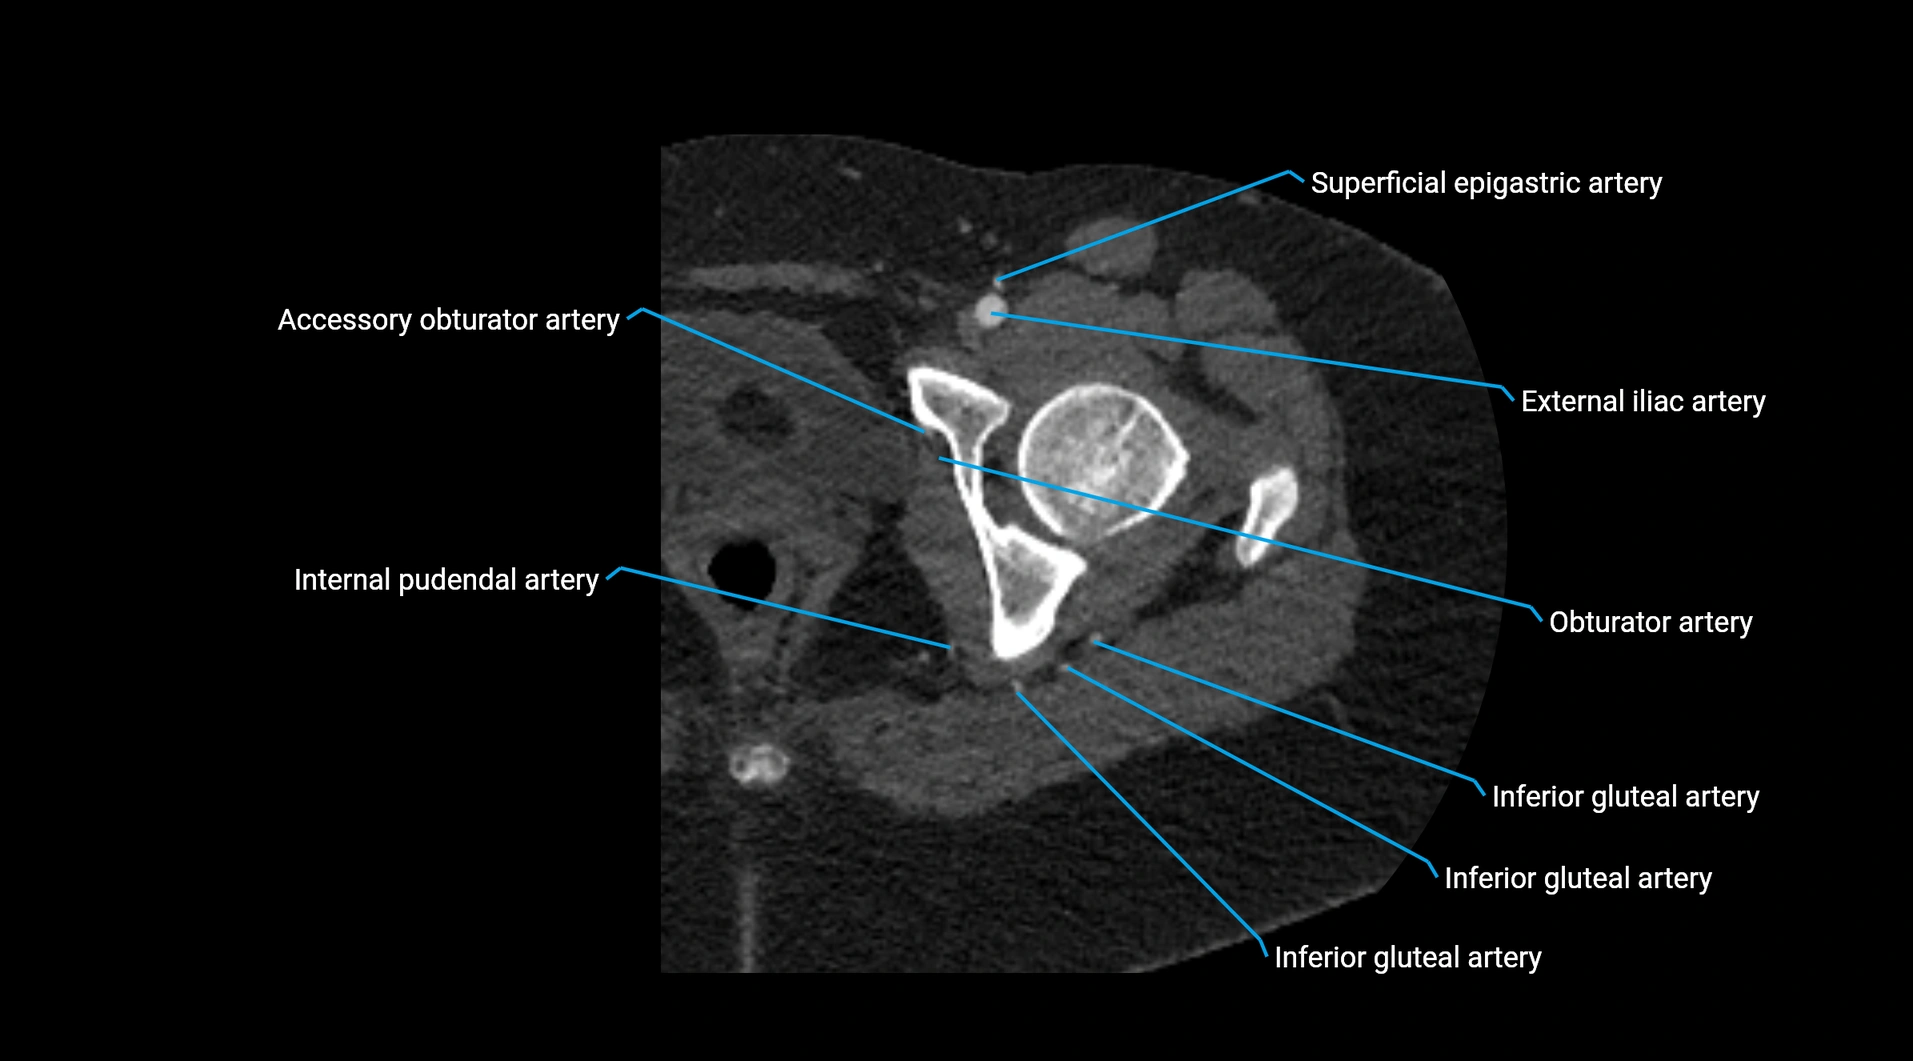

CT images

image

Contrast-enhanced CT (CTA):

• Gold standard for abdominal aortic imaging

• Provides excellent detail of lumen, wall, aneurysm, thrombus, and branch vessels

• Multiplanar and 3D reconstructions help in aneurysm measurement, stent graft planning, and dissection evaluation

• Detects acute rupture, traumatic injury, or occlusion with high sensitivity